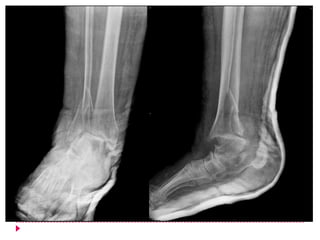

   Diagnóstico

   Historia clínica

   Radiografías AP, lateral y oblicuas

   Rx comparativas *

Valoración radiográfica

   SUPERPOSICIÓN TIBIOPERONÉA(la situación

posterior del peroné con relación a la tibia determina que

al tomar los Rx AP se observe sobreposición de los dos

huesos)

   > 10 mm

   < Lesión de la SINDESMOSIS (permite que se abra la mortaja

tibio-peronéa)

   CLARO TIBIO-PERONÉO (Espacio existente entre el

borde medial del peroné al nivel de la

sindesmosis, a 1 cm por arriba del maleolo de la

Tibia)

   < de 5 mm - 6 mm

   Angulo talo-crural – es el ángulo existente entre

una línea paralela a la superficie articular del

―plafón‖ tibial y otra línea que una los puntos más

distales de los dos maléolos. Este ángulo refleja la

diferencia de longitudes del maléolo externo y

medial y su valor oscila entre los 8 y los 15 grados.

Cuando el valor es menor se debe sospechar

acortamiento del peroné por fractura en el mismo.